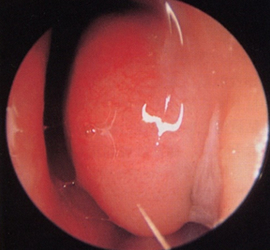

体が外から物質を取り込んだときに過剰に反応を起こしてしまうことをアレルギーといいます。特に鼻で症状が強く出ている状態をアレルギー性鼻炎といいます(図7)。

くしゃみ、鼻水、鼻づまりが3大症状といわれています。慢性副鼻腔炎の鼻汁とは性状が大きく異なり、水っぽくてさらさらした鼻汁が特徴的です。

水っぽい鼻汁が多く出ている鼻粘膜